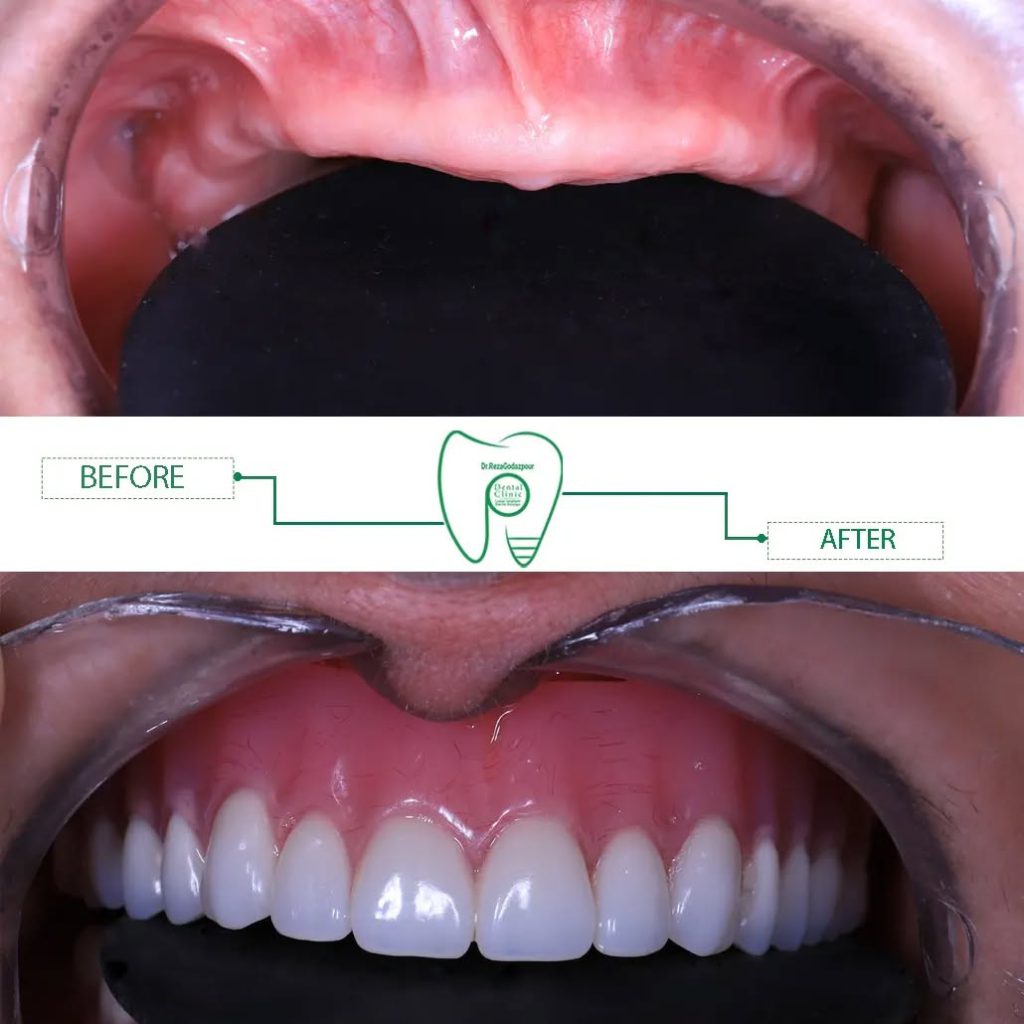

مزایای ایمپلنت شامل بهبود قدرت جویدن، حفظ ساختار استخوان فک، جلوگیری از تحلیل لثه و بازگرداندن ظاهر طبیعی دندان است. ایمپلنت همچنین اعتماد به نفس فرد را بالا میبرد، زیرا دیگر نیازی به پنهان کردن لبخند یا ترس از افتادن دندان مصنوعی وجود ندارد.

مزایای ایمپلنت فوری شامل کاهش تعداد جلسات درمان، کمتر شدن درد و تورم، و بازگرداندن سریع ظاهر طبیعی دندان است. این روش برای افرادی که به سرعت نیاز به جایگزینی دندان دارند یا از مسائل زیبایی اهمیت میدهند، ایدهآل است.